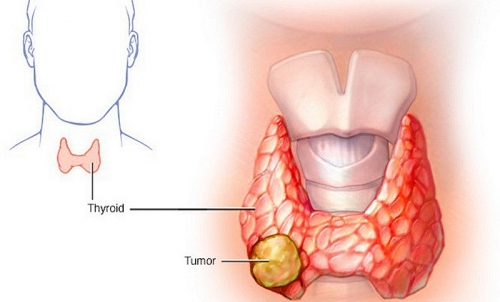

Ung thư tuyến giáp giai đoạn đầu sống được bao lâu?

Ung thư tuyến giáp giai đoạn đầu sống được bao lâu là thắc mắc của nhiều người khi nhận tin mình mắc bệnh. Giải đáp ngay trong bài viết sau!

Triệu chứng ung thư tuyến giáp giai đoạn đầu

Những triệu chứng ung thư tuyến giáp giai đoạn đầu là gì và cần làm thế nào để phòng tránh ung thư tuyến giáp?

Dấu hiệu ung thư tuyến giáp giai đoạn cuối

Dấu hiệu ung thư tuyến giáp giai đoạn cuối bao gồm những gì? Liệu có cách chữa trị nào khi đã tới ung thư tuyến giáp giai đoạn cuối?

Triệu chứng u tuyến giáp ác tính

Triệu chứng u tuyến giáp ác tính bao gồm những gì? U tuyến giáp ác tính có thể chữa dứt điểm khỏi bệnh hay không?

Biểu hiện ung thư tuyến giáp

Biểu hiện ung thư tuyến giáp là gì? Ung thư tuyến giáp có nguy hiểm chết người hay không?

Triệu chứng u tuyến giáp lành tính

Triệu chứng u tuyến giáp lành tính là gì? Khi không may mắc phải thì có thể chữa được không?